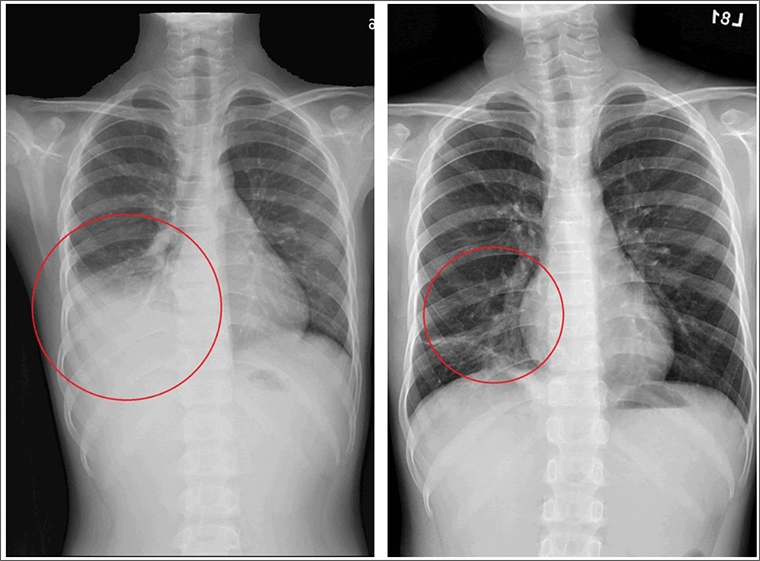

台北慈濟醫院小兒感染科醫師吳秉昇說,個案許小弟在就診時,院方便透過抽血及胸部X光檢查發現其體內的C反應蛋白(一種發炎指數)偏高且右下肺葉有感染情形,聽診也發現有囉音及喘鳴,診斷為社區性肺炎。另外因其黴漿菌急性抗體呈現陽性,懷疑為肺炎黴漿菌感染,考量情況較為嚴重,便收治住院觀察。

不料病情瞬息萬變,在經抗生素治療後,許小弟仍然高燒未退甚至出現肺炎擴散及肋膜積水的情形,後來透過黴漿菌抗生素的調整,當晚許小弟即逐漸退燒,且在1週後平安出院,後續胸部X光追蹤亦發現右下肺炎及肋膜積水已改善。